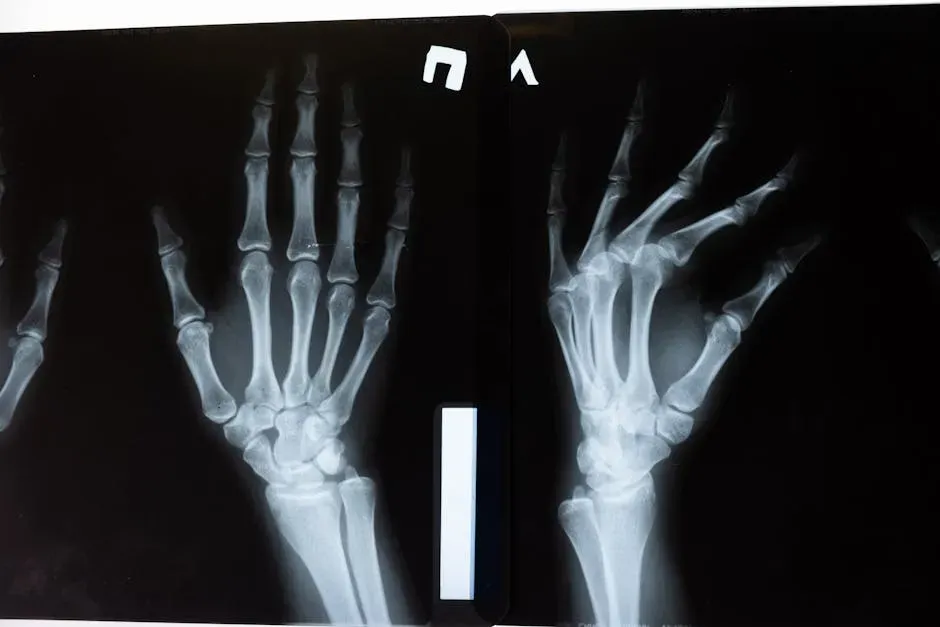

Bone Remodeling: The Skeleton That Rebuilds Itself

Your skeleton seems like a rigid, permanent structure, but it’s surprisingly dynamic. Throughout your life, specialized cells are constantly breaking down old bone and building new bone in a process called remodeling. Over the span of roughly a decade, much of your skeleton has effectively been renewed, even though it feels completely solid the whole time.

This is more than just maintenance; it’s adaptation. When you put stress on your bones through walking, lifting, or exercise, they respond by getting denser and stronger in the areas that need it most, like a bridge being reinforced where traffic is heaviest. Sit too much or avoid loading your body, and the opposite can happen: bones weaken because there’s no signal to keep them robust. It’s a quiet reminder that your everyday habits are literally shaping your structure.